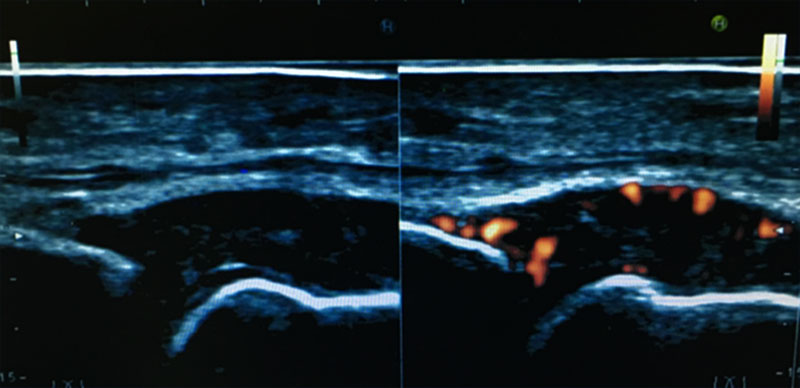

RA診療においても、関節エコーはリウマチ性疾患に特徴的な炎症や骨破壊を鋭敏に捉えることができ(図8)、リウマチ診療においても診断や疾患活動性評価に有用とされています。AORAでは、関節エコー技術の普及を目的に、AORAメンバーのみならず、関連病院の検査技師の方々を対象として、勉強会を開催しエコー技術の普及を行なっております。関節エコーにより、より高度なRA診療を目指しています。

図8 RA患者さんの関節エコー画像